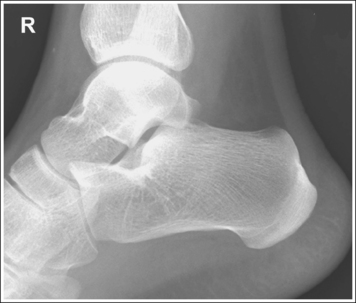

The ankle is in a lateral projection. The domes of the talus are superimposed, the tibiotalar joint is open, and the distal fibula is superimposed by the posterior half of the distal tibia.

• To obtain a lateral ankle projection, begin with the patient in a supine position, with the leg extended (Figure 6-57) and the foot dorsiflexed until its long axis forms a 90-degree angle with the lower leg. Rotate the patient and affected leg until the lateral foot surface is against the IR, and then adjust the degree of rotation until the surface is aligned parallel with the IR (Figure 6-58). For most patients, this positioning places the lower leg parallel with the imaging table. If this is not the case, as with a patient with a large upper thigh, the foot and IR should be elevated until the lower leg is parallel with the imaging table.

• Effect of lower leg positioning on talar dome superimposition. Often, if the knee is not fully extended (Figure 6-59) or if the distal tibia is not elevated to place the lower leg parallel with the IR in a patient with large upper thighs, the proximal tibia is positioned farther from the imaging table than the distal tibia. The resulting image demonstrates the lateral talar dome proximal to the medial talar dome and the height of the longitudinal arch appears less than it actually is because the cuboid shifts anteriorly and the navicular bone moves posteriorly in this position and the talocalcaneal joint will be narrowed (see Image 43). If the distal tibia is positioned farther from the table than the proximal tibia, the medial talar dome is demonstrated proximal to the lateral dome, and the height of the longitudinal arch appears greater than it actually is because the cuboid shifts posteriorly and the navicular bone moves anteriorly in this position and the talocalcaneal joint will be widened (see Image 44). When viewing a lateral ankle projection that demonstrates one of the talar domes proximal to the other, evaluate the height of the longitudinal arch and the degree of talocalcaneal joint visualization to determine which dome is the proximal dome. If the navicular bone is superimposed over more of the cuboid than expected and a narrowed talocalcaneal joint is seen, the lateral dome is the proximal dome. If the navicular bone is superimposed over less of the cuboid than expected and a wider talocalcaneal joint is seen, the medial dome is the proximal dome.

• Effect of foot positioning on talar dome superimposition. To demonstrate accurate AP alignment of the talar domes, position the lateral surface of the foot parallel with the IR. If this surface is not parallel with the IR, the talar domes are demonstrated one anterior to the other. When the leg is rotated more than needed to place the lateral foot surface parallel with the IR (leg externally rotated), as shown in Figure 6-60, the medial talar dome is demonstrated anterior to the lateral talar dome (see Image 45). If the leg is not rotated enough to place the lateral foot surface parallel with the IR (leg internally rotated), as shown in Figure 6-61, the medial talar dome is demonstrated posterior to the lateral talar dome (see Image 46). When taking a lateral ankle projection that demonstrates one of the talar domes anterior to the other, observe the position of the fibula in relation to the tibia to determine how the patient should be repositioned. On most lateral ankle projections with accurate positioning, the fibula is positioned in the posterior half of the tibia. On a lateral projection with poor positioning, if the fibula is demonstrated more posteriorly, the medial dome is anterior and the patient was positioned with the forefoot depressed and the heel elevated (leg externally rotated), as shown in Figure 6-60. If the fibula is demonstrated more anteriorly, the medial domes are posterior and the patient was positioned with the forefoot elevated and the heel depressed (leg internally rotated), as shown in Figure 6-61.

The long axis of the foot is positioned at a 90-degree angle with the lower leg.

• In most cases, when the patient is relaxed, the foot rests in plantar flexion. Plantar flexion results in a forced flattening of the anterior pretalar fat pad, reducing its usefulness in the detection of joint effusion (see Image 47). Consequently, it is best to dorsiflex the patient's foot, placing its long axis at a 90-degree angle with the lower leg. This positioning also places the tibiotalar joint in a neutral position and helps prevent the leg from rolling too far anteriorly. Anterior foot rotation elevates the heel and rotates the foot.